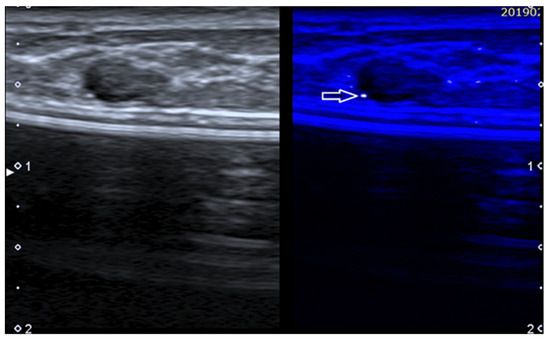

Figure 6. Fibroadenoma in a patient with history of augmentation mammoplasty. MicroPure allows to easily detect a bright dot (arrow) due to a small calcification.

Grouped microcalcifications represent a very important finding in breast imaging and a significant US limitation, being hard or impossible to detect, particularly if not associated with a nodule [75]. MicroPureTM is a software from Canon (Tokyo, Japan) that allows to highlight microcalcifications (Figure 6).

MicroPure combines non-linear imaging with speckle suppression, extracting the calcification from the heterogeneous background. Filtered microcalcifications are shown as bright dots inside a dark blue background overimposed to a grayscale US.